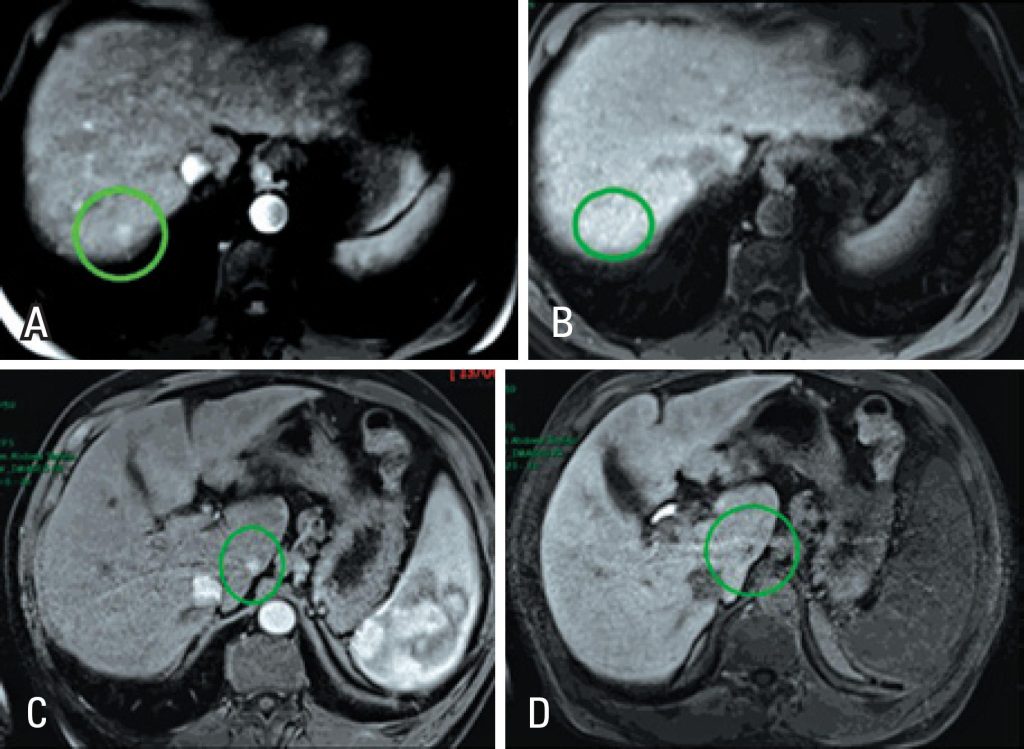

The hepatobiliary-specific contrast medium (gadoxetic acid – Primovist®) is primarily used to improve detection and characterization of focal hepatic lesions, such as in chronic liver disease patients with suspected hepatocellular carcinoma. Since the contrast medium is selectively taken up by functioning hepatocytes in the late hepatobiliary phase, it helps to detect typical hepatocellular carcinoma, which show low signal intensity on this phase. This imaging feature also assists in differentiating regenerative/dysplastic nodules from early hepatocellular carcinomas (with over 90% accuracy), as well as hypervascular hepatocellular carcinomas from arterial pseudo-enhancement foci. Future perspectives include its use in quantification of hepatic function and fibrosis.